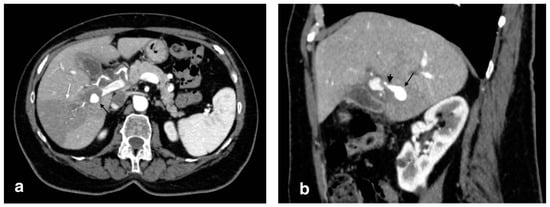

Figure 2.

Gangrenous cholecystitis: irregular wall thickening with bulging and focal defects in the gallbladder wall (black arrows, (a)). Coexisting hepatic hyperemia (arrowheads) and pericholecystic fluid (white arrows) (a,b).